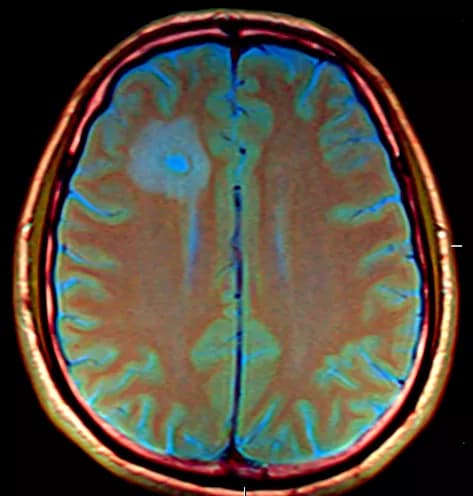

Glioma is one of the most common types of cancerous tumors originating in the brain. It begins in the cells that surround nerve cells and help them function. The disease is typically diagnosed in middle age. At present, there is no treatment that ensures long-term survival, but several potential options are being studied.